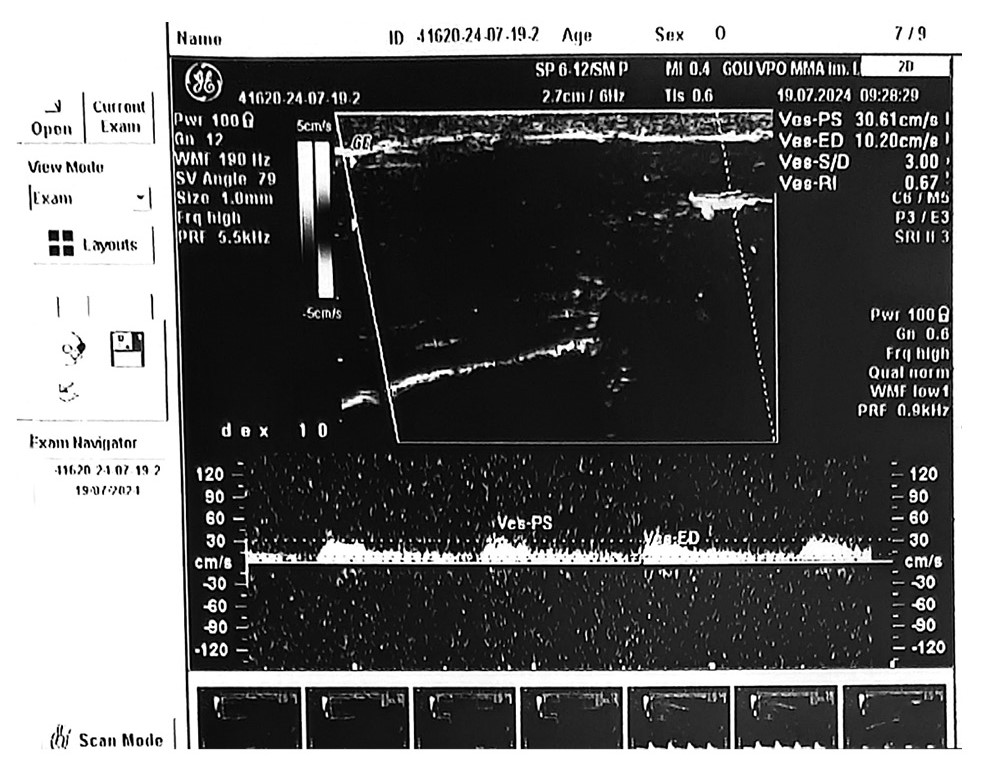

В Научно-практическом центре интервенционной кардиоангиологии пациента полностью обследовали. Клинико-биохимические лабораторные показатели – в норме, тестостерон – 31,8 нмоль/л. Пациенту провели фармако-индуцированную эходопплерографию ПЧ и МСКТ-кавернозографию. По данным эходопплерографии ПЧ (ультразвуковой системы GE Voluson 730) структура кавернозных тел и белочной оболочки однородная. Определяются контуры правой и левой кавернозных артерий. Стенки артерий четкие и ровные на протяжении всей области сканирования. В режиме цветного допплеровского картирования четко выявлен кровоток в проекции проксимальных отделов кавернозных артерий. После нагрузки 10 мкг простагландина Е1 эрекцию отмечали через 10 мин. На фоне фарминдуцированной эрекции регистрируется значимое повышение пиковой систолической и конечной диастолической скорости кровотока в обеих кавернозных артериях. Линейная скорость кровотока по глубокой дорзальной вене ПЧ составила 47,7 см/с (рис. 1). Начало детумесценции произошло через 40 мин.

Рис. 1. Данные эходопплерографии ПЧ с фармакологической стимуляцией больного К.